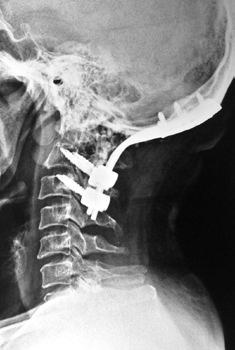

c0 c1 c2 fixation

c1 c2